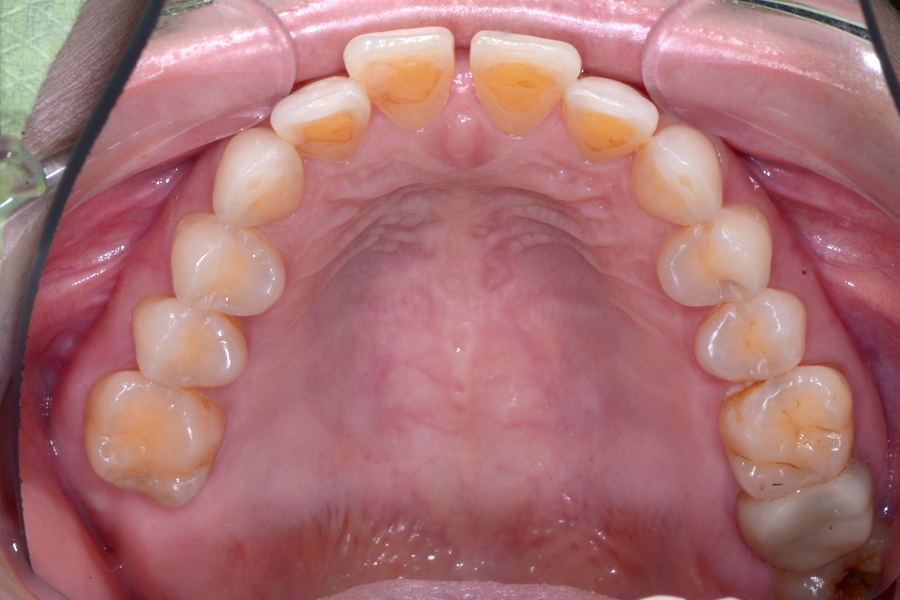

• 治療後